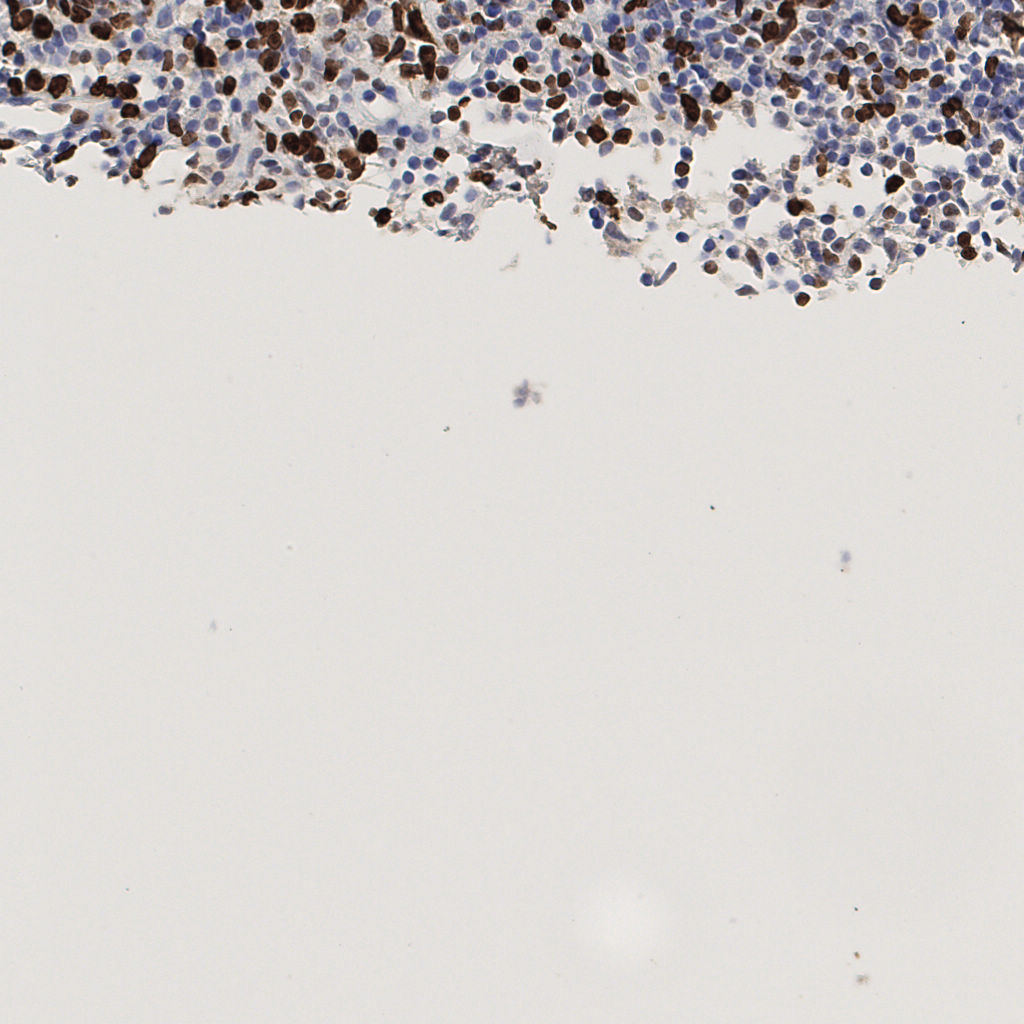

7.85%

Ki67 指数

阴 1104 阳 94

切片统计

总切片 1953

有效 288

已标记 288

有效率 15%